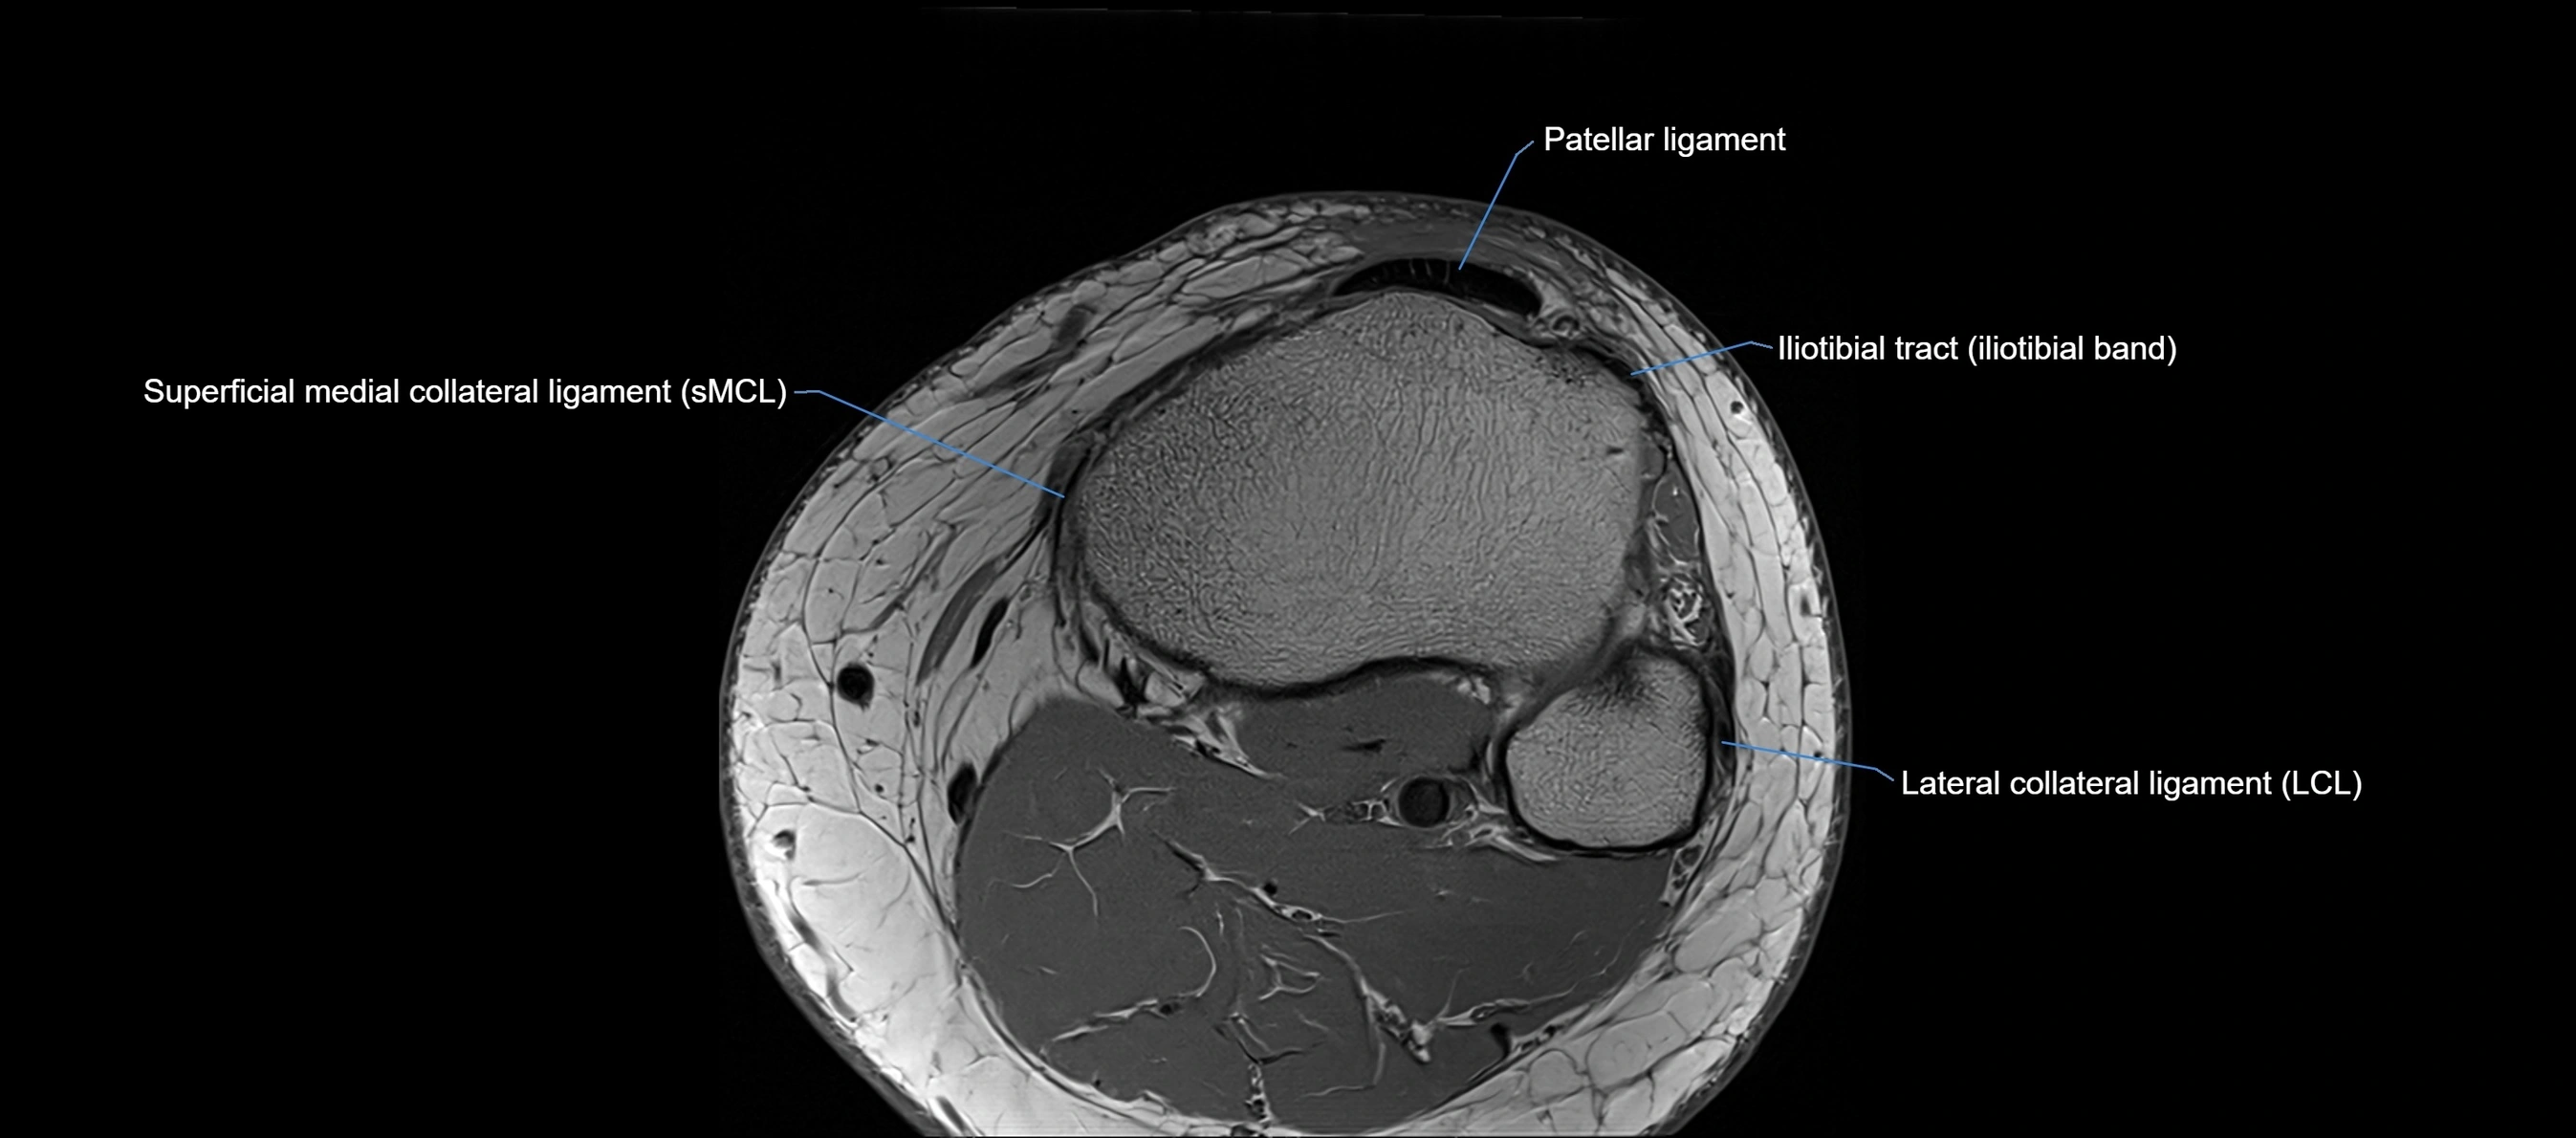

MRI images

image